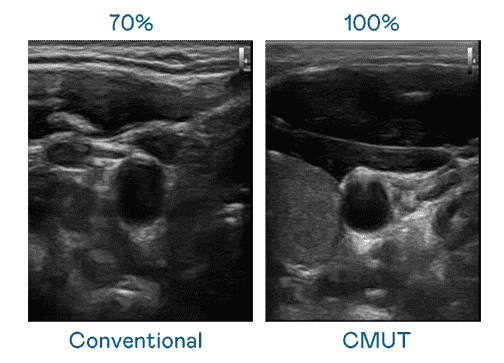

CMUT 技术是一种用电容式微机电元件来产生超音波讯号的技术。。与传统 PZT 压电式技术相比,,CMUT 频宽增加 30%,,更宽频的超音波讯号让影像解析度大幅提升,,是实现高影像品质医疗超音波扫描、、促进精准医疗发展的关键技术。。。

大频宽带来超清晰影像

超音波影像的解析度高低,,,首先取决于探头能发出的讯号频宽。。。。JDB电子 CMUT 可提供高清晰的超音波讯号,,提供高频宽、、高灵敏度、、影像纹理细节更高的超音波影像,,,,协助医护人员缩短影像判读时间及利用精准的医疗影像进行诊断。。。。